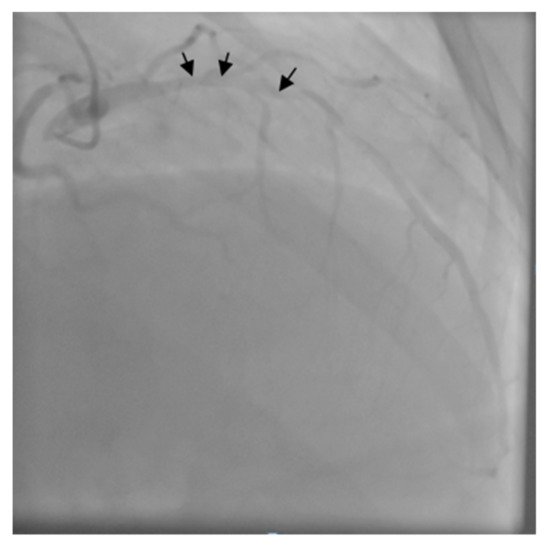

After the gastrectomy, the patient underwent X-ray radiography (Figure 4). Four weeks later, the patient developed a marked inflammatory syndrome (erythrocyte sedimentation rate (ESR) 100 mm, White Cell Count (WCC) 20,000, C-Reactive Protein test (CRP) 30, raised procalcitonin test, and pyrexia). The clinical examination revealed a diastolic aortic murmur with collapsing pulses. The transthoracic ECHO detected multiple aortic leaflet vegetations with severe regurgitation (grade IV). Blood cultures identified Staphylococcus saprophytic. As there was no existence of dental infections, malnutrition, or preexistent aortic lesions, due to the cancer and preexistent co-morbidities, the patient developed a paraneoplastic immune depression that resulted in the Staphylococcus saprophytic infection.

Figure 4. Radiological image after total gastrectomy and gastrojejunoanastomosis.